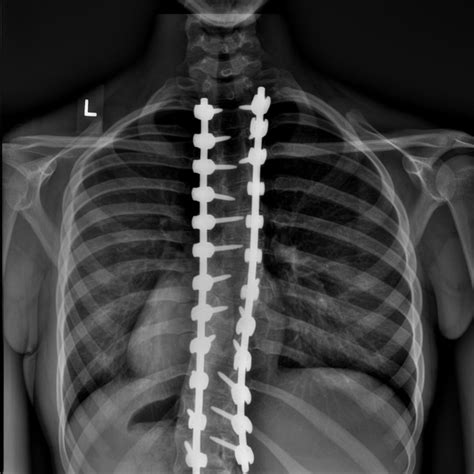

• Scoliosis and Deformities: Severe curvatures of the spine often require fusion to prevent the condition from worsening and to maintain proper alignment.

At its core, spinal fusion is a surgical procedure designed to permanently connect two or more vertebrae in the spine. By eliminating the motion between these segments, the surgery aims to reduce pain, improve stability, and correct deformities. It is essentially a "welding" process where a bone graft is placed between the vertebrae, eventually causing them to grow together into one solid bone.

When investigating when is spinal fusion necessary, physicians look at a specific set of clinical conditions that compromise the structural integrity of the spinal column. These conditions generally fall into three categories: instability, deformity, and severe nerve compression.